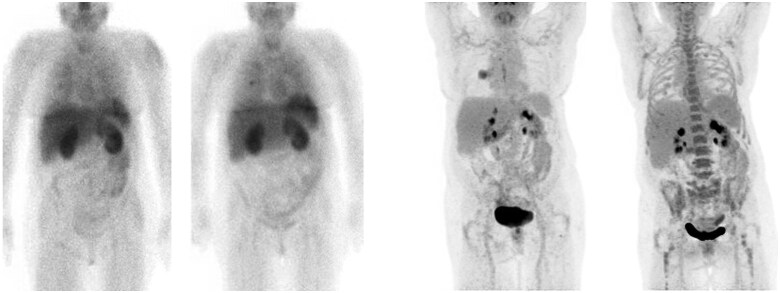

Objectives: To investigate how anti-PD-1 treatment affects both Programmed Death-Ligand 1 (PD-L1) expression and glucose metabolism within normal tissues of advanced non-small cell lung cancer (NSCLC) patients using a dual SPECT/CT and PET/CT imaging approach.

Methods: Ten advanced NSCLC patients (NCT04436406) undergoing anti-PD-1 therapy ± chemotherapy underwent imaging at baseline and 9 weeks. PD-L1 expression was measured using [99mTc]-labelled single-domain PD-L1 antibody single-photon emission computed tomography/computed tomography ([99mTc]NM-01 SPECT/CT). Glucose uptake was measured using [18F]-Fluorodeoxyglucose positron emission tomography/computed tomography ([18F]FDG PET/CT). Two independent observers marked regions of interest across normal organs (liver, lung, spleen, bone marrow, muscle, kidney, pancreas, left ventricular myocardium, and blood pool) to determine maximum and mean standardized uptake values (SUV) at both time points. Observer agreement was measured with an intraclass correlation coefficient (ICC).

Results: No significant changes in SUVs, indicating PD-L1 expression and glucose metabolism, were detected in normal organs after 9 weeks of treatment (all P > .05). No patients developed immune-related adverse events (irAEs) during the study period. Observer measurements showed excellent consistency with an ICC of 0.99 (95% confidence interval 0.99-0.99).